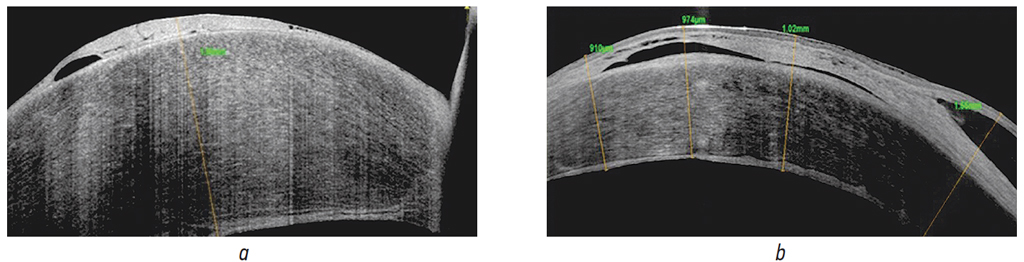

По данным биомикроскопии во всех случаях отмечался выраженный отёк роговицы, буллёзные изменения эпителия с грубым нарушением визуализации структур переднего отдела глаза (рис. 1).

Рис. 1. Пациент М. Буллёзная кератопатия IV стадии: а — выраженный эпителиально-стомальный отёк роговицы с буллами эпителия; b — эпителий удалён, выраженный стомальный отёк роговицы, грубое нарушение прозрачности роговицы

Fig. 1. Patient M. The stage IV of bullous keratopathy: а — severe epithelial-stromal edema of the cornea with bullous epithelium; b — the epithelium is removed; severe corneal stromal edema, gross impairment of corneal transparency are present

В четырех случаях отмечалось наличие поверхностной и глубокой неоваскуляризации роговицы в периферических и парацентральных отделах (рис. 2).

Рис. 2. Пациент К. Буллёзная кератопатия V степени: а — выраженный эпителиально-стомальный отёк роговицы с буллами эпителия и поверхностной неоваскуляризацией; b — эпителий удалён, выраженный стомальный отёк роговицы с глубокой неоваскуляризацией

Fig. 2. The stage V of bullous keratopathy: а — severe epithelial-stomal corneal edema with epithelial bullosis and superficial neovascularization; b — the epithelium is removed; severe corneal stromal edema with deep neovascularization is present